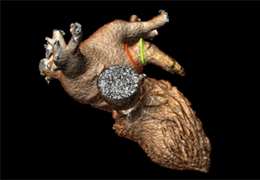

View X-Ray CT & MRI Scans Fast and Easily

Designed for surgeons, Pro Surgical 3D makes it easy to view patient scans quickly. Pro Surgical 3D facilitates the optimal 3D treatment and assessment workflows based on X-ray CT and MRI scans – and best of all, it’s FREE!

Everyone – including surgeons, patients and their loved ones – benefits from being better informed by the wealth of information buried within CT and MRI scans. Pro Surgical 3D gives surgeons more information to develop optimal treatment plans for patients. It also helps patients and their support group better understand their medical condition and proposed treatment options.

High-quality and fast 3D reconstruction and 3D rendering

Performs 3D reconstruction and volume rendering.

Instant and interactive surface extraction and export to STL and PLY formats.